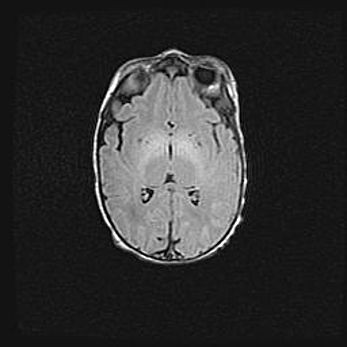

Церебральная ишемия II.

Возраст: 5 дней

Вес: 3400 г

Пол: женский

Окружность головы: 35 см

Срок гестации: 39 недель

Церебральная ишемия – это заболевание, характеризующееся недостаточностью (гипоксией) либо полным прекращением (аноксией) снабжения мозга кислородом по причине закупорки одного или нескольких сосудов. Это приводит к  что метаболическим расстройствам различной степени тяжести в тканях головного мозга, развитию коагуляционных некрозов и гибели нейронов.